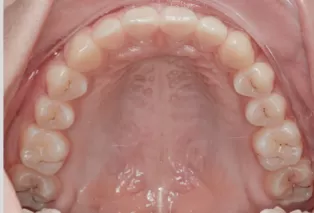

Intraoral photos after treatment